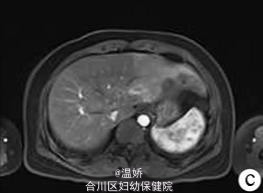

人肝片形吸虫病1例报告

患者,女,41岁,因肝区胀痛2个月余人院。2个月前无诱因出现肝区胀痛,伴发热(体温最高38℃),当地医院予抗感染后疼痛症状缓解,体温下降但此后症状时有反复发作。入院1d前当地医院腹部CT平扫提示肝左叶低密度灶。